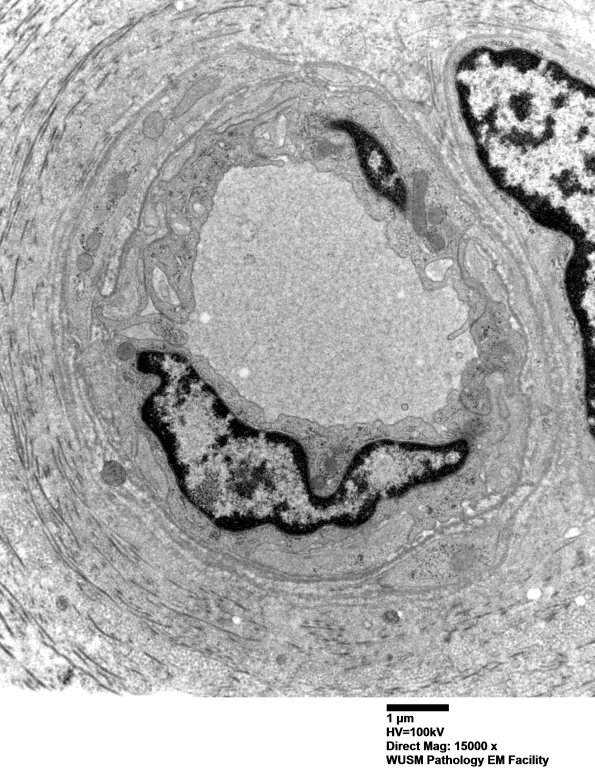

The vessels are mildly enlarged by basal lamina and collagen. (electron micrograph)